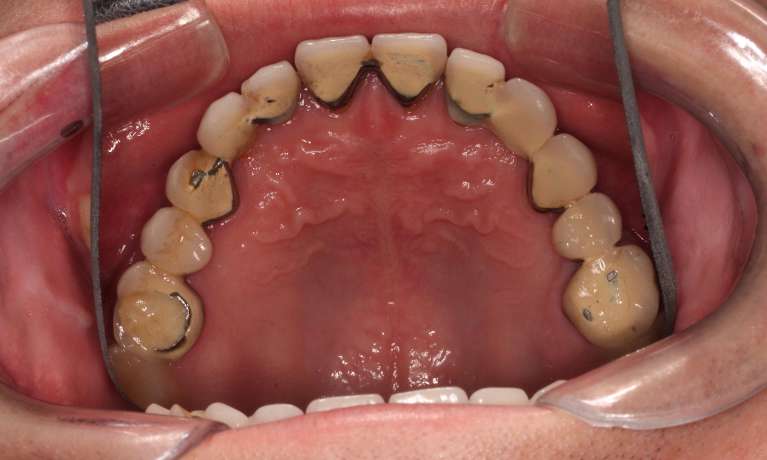

This adult patient had heavily restored discolored and defective upper front teeth. Their upper front four teeth were rejuvenated with new crowns to give the finished smile.